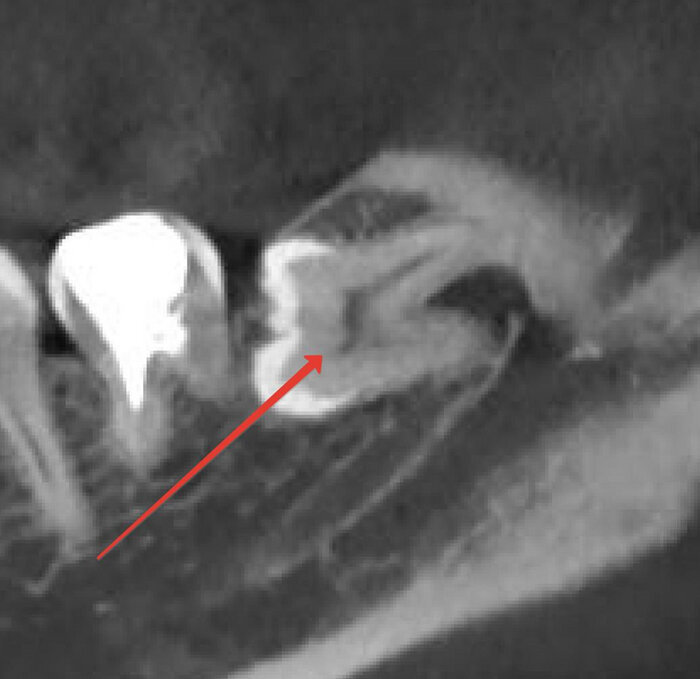

Теперь вид в разрезе, то есть ради чего и делалась эта томография. Тут мы увидим детальнее расположение нижнего альвеолярного нерва, который многие путают с лицевым. Этот нерв располагается вплотную к корню и если его повредить, то у пациента возникнет онемение нижней губы и подбородка с одной стороны.

-4